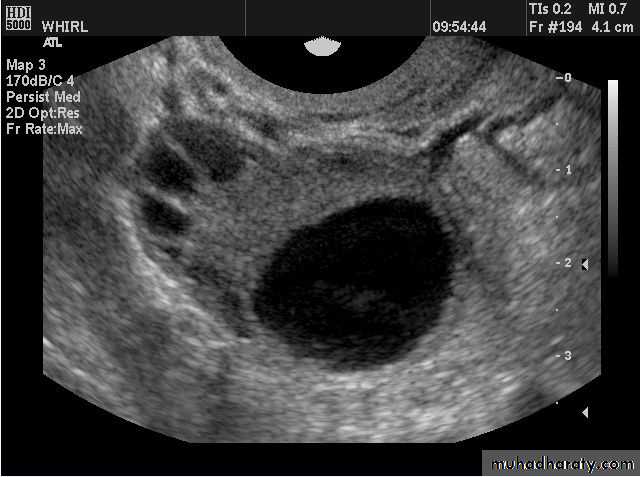

• Functional cysts of the ovary – Corpus Luteum cysts

Lt. adnexal cystic mass- Luteal cyst(Lt. ovary):

Rt. ovarian simple cyst: